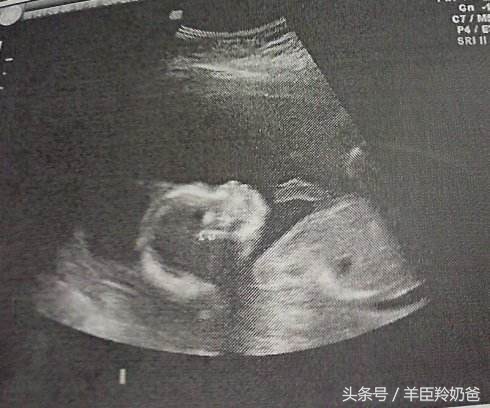

这个时期是做B超的最合适的时间,也是最重要的一次检查,在这个阶段能够通过B超检查胎儿的发育情况、能检查出胎儿是否有畸形,对胎儿的位置和羊水量也有一定的了解。